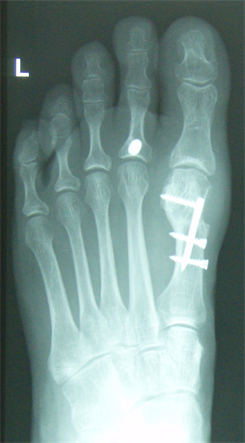

Figure 6. Patient Nr. 1. After 6 months the bone healing is completed with no loss of correction. Immediate full weigh bearing was allowed.